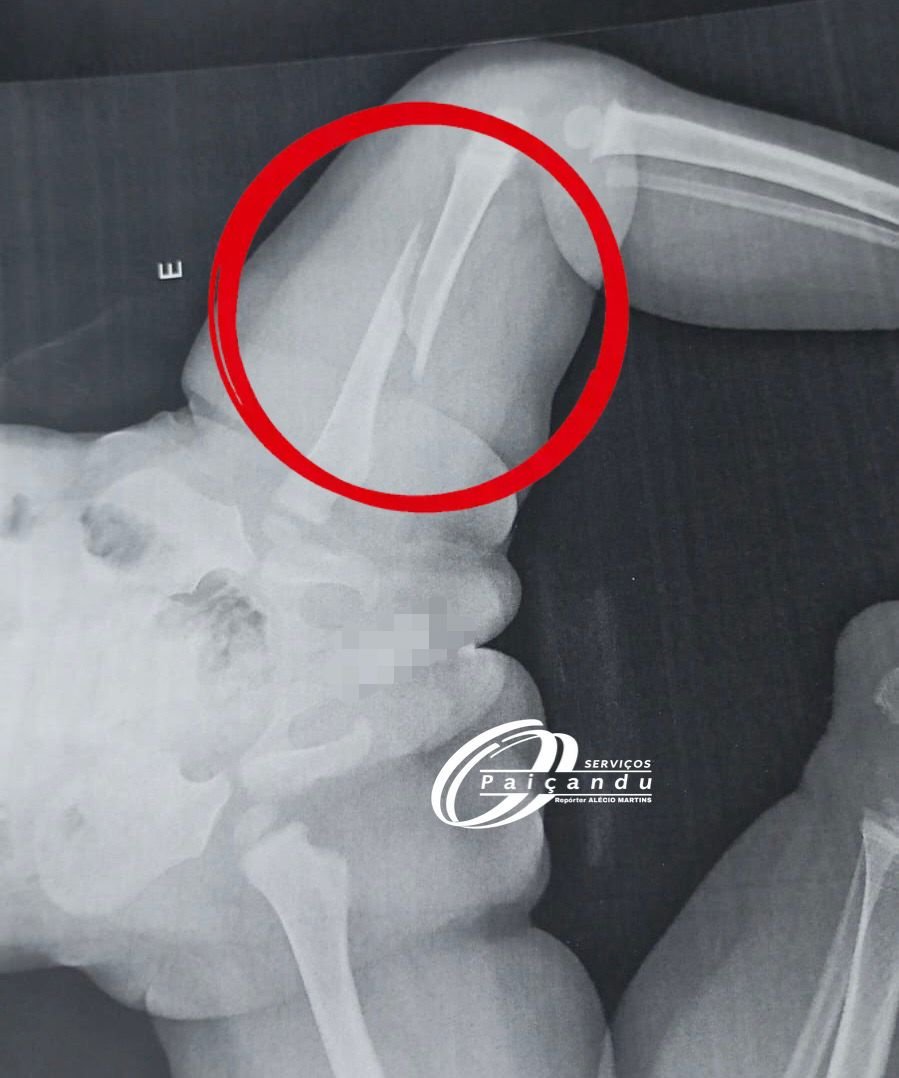

Uma criança de 1 ano e 5 meses deu entrada no Hospital Santa Maria, no município de Floresta, neste sábado, dia 07, apresentando fraturas em diferentes partes do corpo. A situação chamou a atenção da equipe médica, que levantou suspeitas quanto à origem das lesões.

Conforme informações repassadas no hospital, a mãe relatou que a criança teria se machucado após uma queda. No entanto, o pai da criança, que é separado da mãe, não concordou com a versão apresentada e registrou um boletim de ocorrência na manhã deste domingo, dia 08, solicitando a apuração dos fatos.

Diante da gravidade do quadro clínico, a criança foi transferida para o Hospital Santa Casa, em Maringá, onde permanece internada sob cuidados médicos.

A Polícia Civil de Paiçandu irá investigar o caso, e aguarda a conclusão dos laudos médicos para confirmar as causas das lesões e esclarecer se houve ou não a prática de crime. Até o momento, todas as informações seguem sendo tratadas como suspeita.